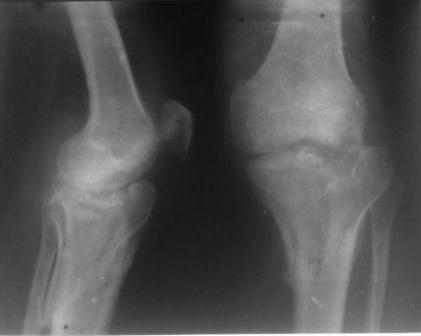

Обратился больной 46л. 3-месяца назад в каком-то городке Дальнего Востока упал с высоты, сделана Р-графия, наложена гипсовая повязка, от предложенной операции отказался и уехал домой, дальше где и как лечился, не говорит.

Ходит при помощи двух костылей, жалобы на боли при нагрузке, в покое и при движении, без нагрузке боли нет, разгибание 175 гр, сгибание 90 гр, симптомов повреждения связочного аппарата к/с не определяется, от предложенного артродеза пока отказывается.

По тактике лечения, более импонирует второй вариант, но наружная плато расколота и туда при нагрузке внедряется н/мышелка бедра, поэтому после дистракции как репонирвать: или стяжными винтами, или изогнутами спицами или субхондральная костная пластика?

У пациента основной проблемой является импрессионый перелом наружного мыщелка, уже неправильно сросшийся, по-видимому. Аппаратом закрыто можно только подправить угол на уровне метадиафиза. Что

улучшит разве что внешний вид конечности, но не решит основной проблемы - грубой деформации суставной поверхности.